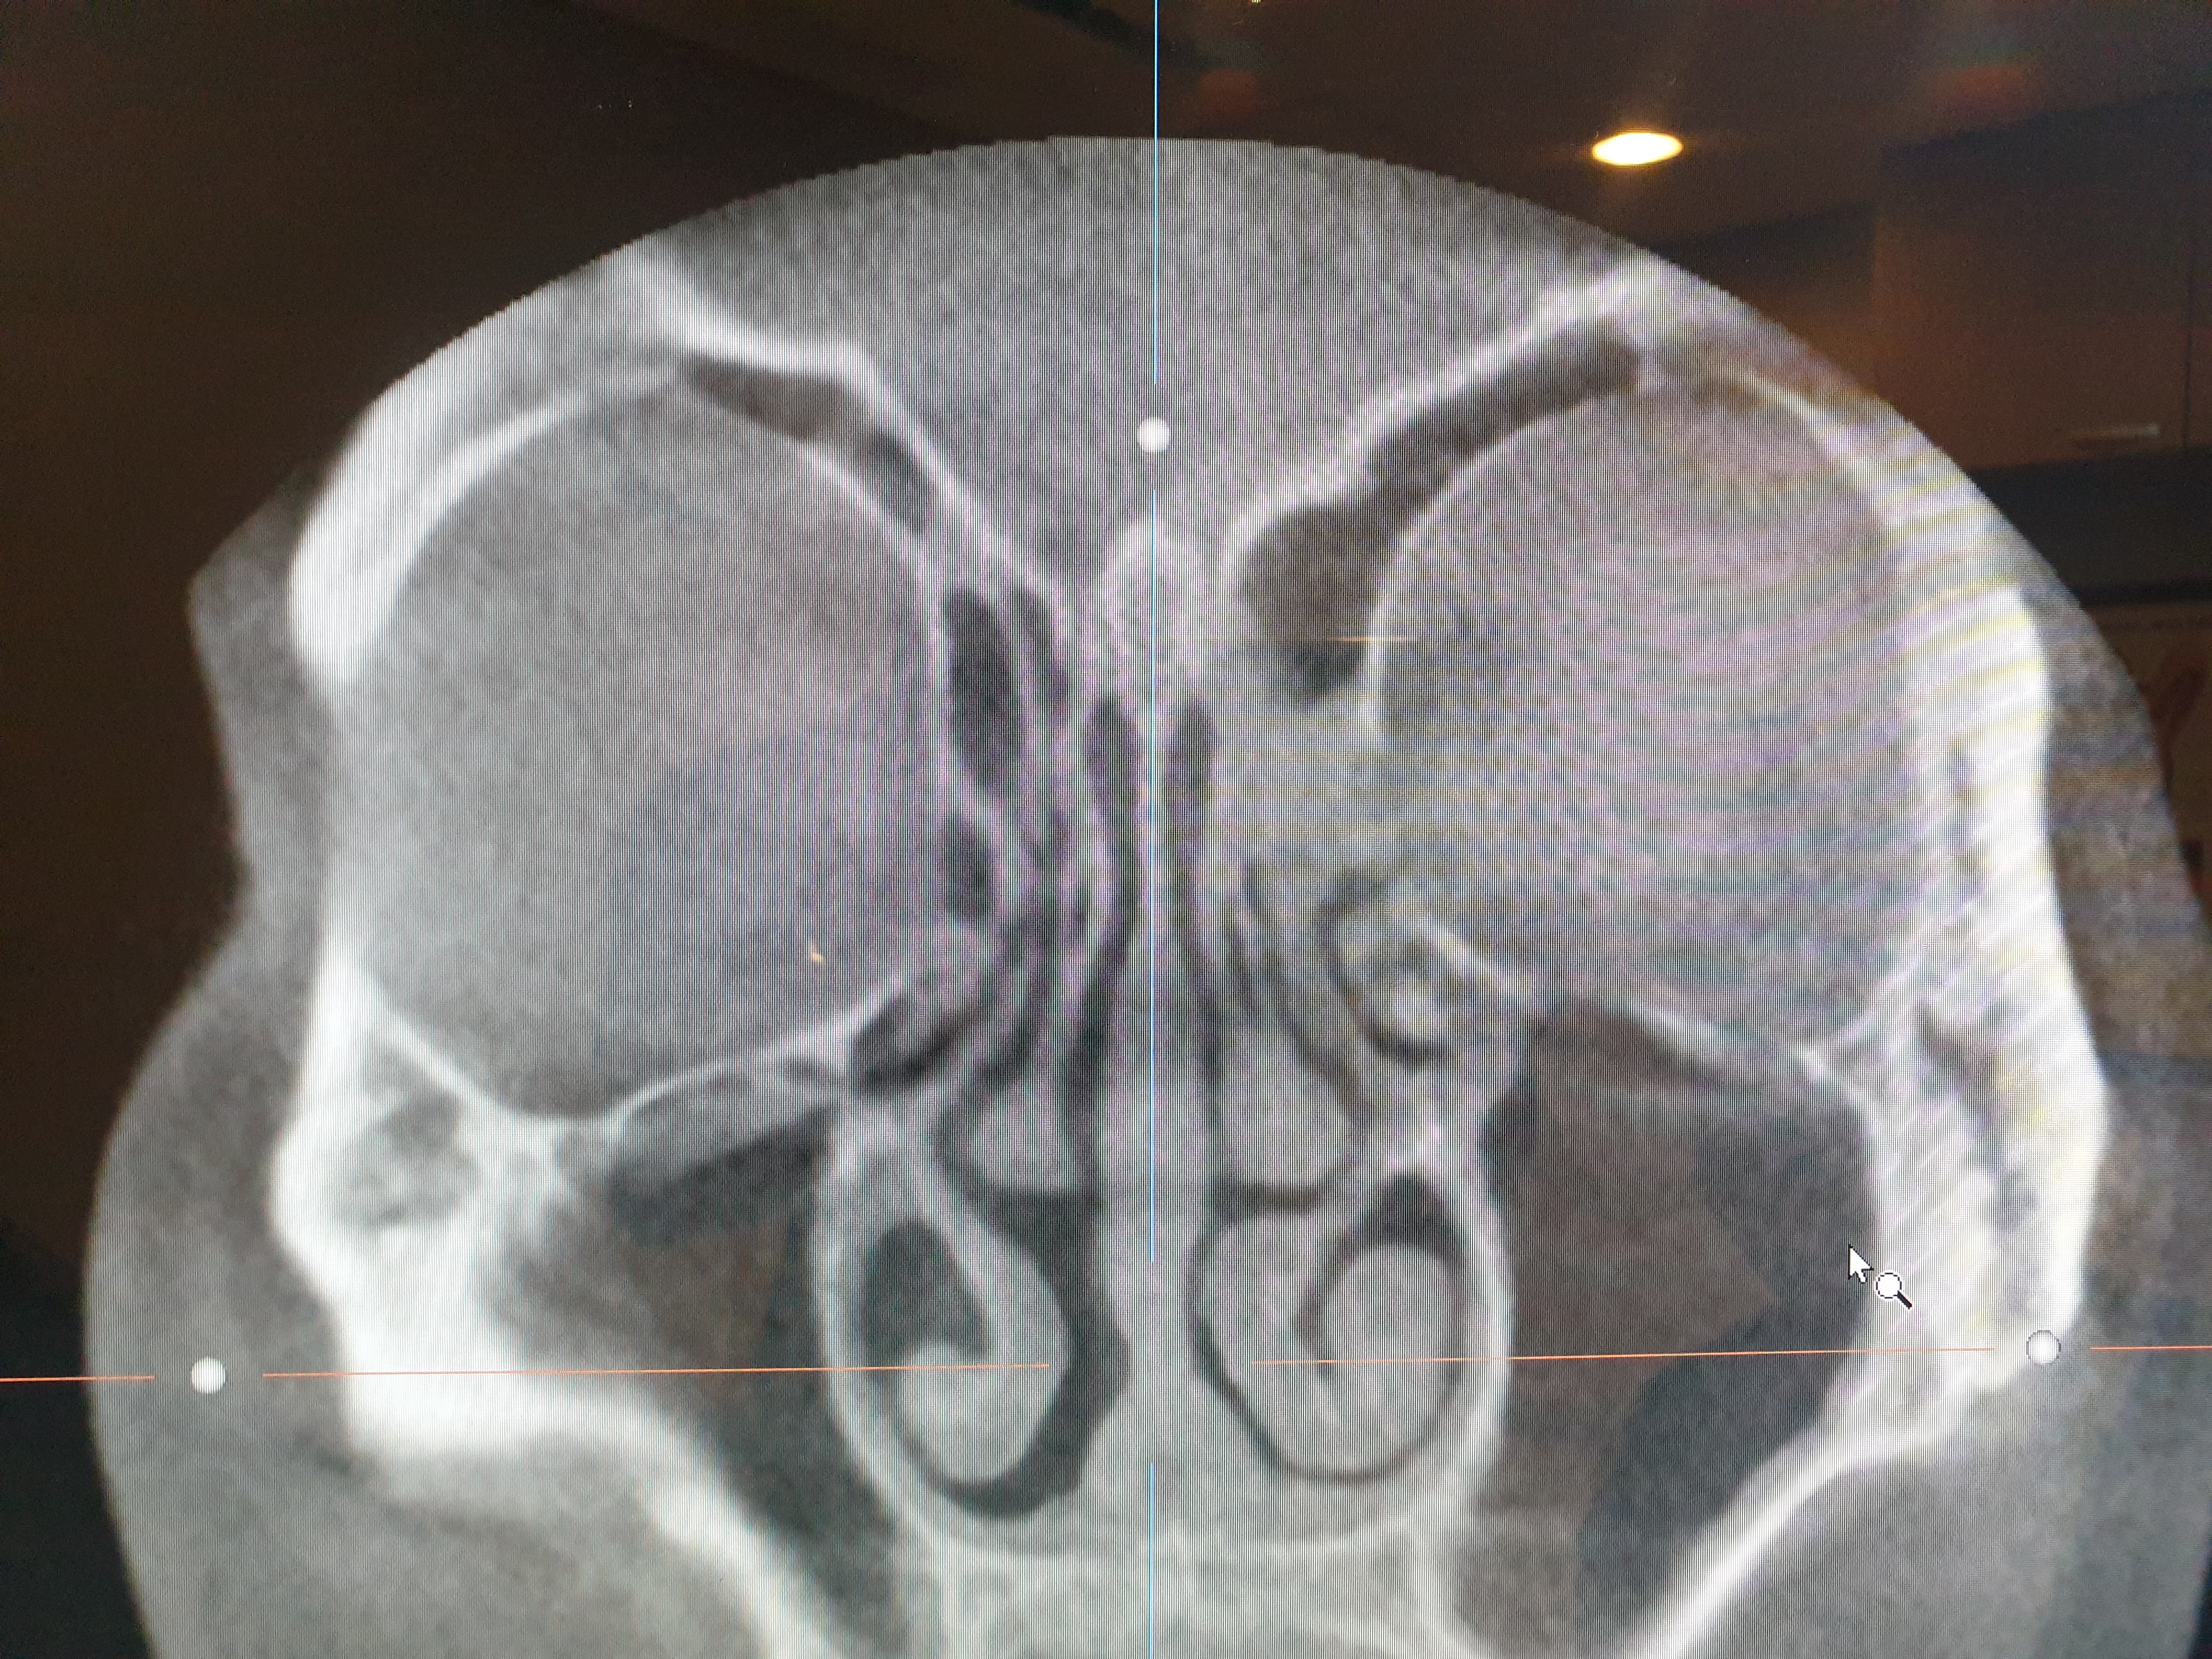

이비인후과에서 엑스레이를 찍었다.

오른쪽 빨간 네모칸을 보면

왼쪽과는 다르게 막혀 있는 것을 볼 수 있다.

의사 선생님 말로는

염증으로 점막이 부어서 막혀 있는 것 같다고 하셨다.